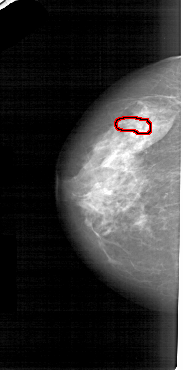

A_1553_1.LEFT_MLO

FILE: A_1553_1.LEFT_MLO.OVERLAY

TOTAL_ABNORMALITIES 1

ABNORMALITY 1

LESION_TYPE CALCIFICATION TYPE PUNCTATE DISTRIBUTION LINEAR

ASSESSMENT 4

SUBTLETY 1

PATHOLOGY BENIGN

TOTAL_OUTLINES 1

BOUNDARY